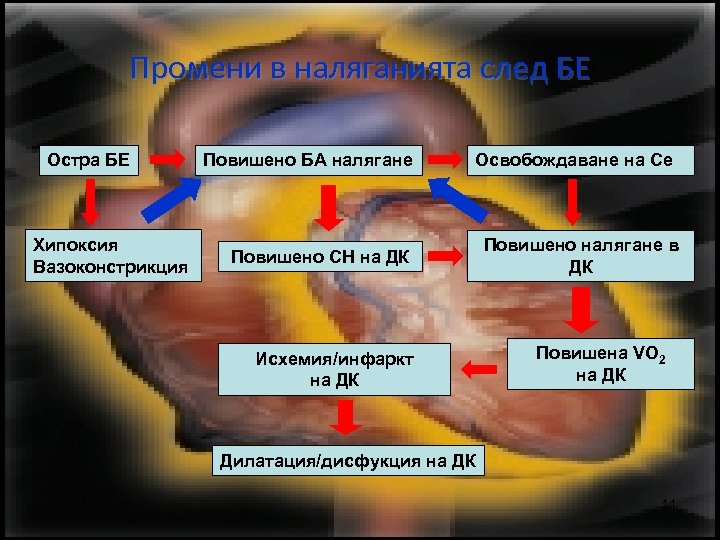

Промени в наляганията след БЕ Остра БE Хипоксия Вазоконстрикция Повишено БА налягане Освобождаване на Се Повишено СН на ДК Исхемия/инфаркт на ДК Повишено налягане в ДК Повишена VO 2 на ДК Дилатация/дисфукция на ДК 11